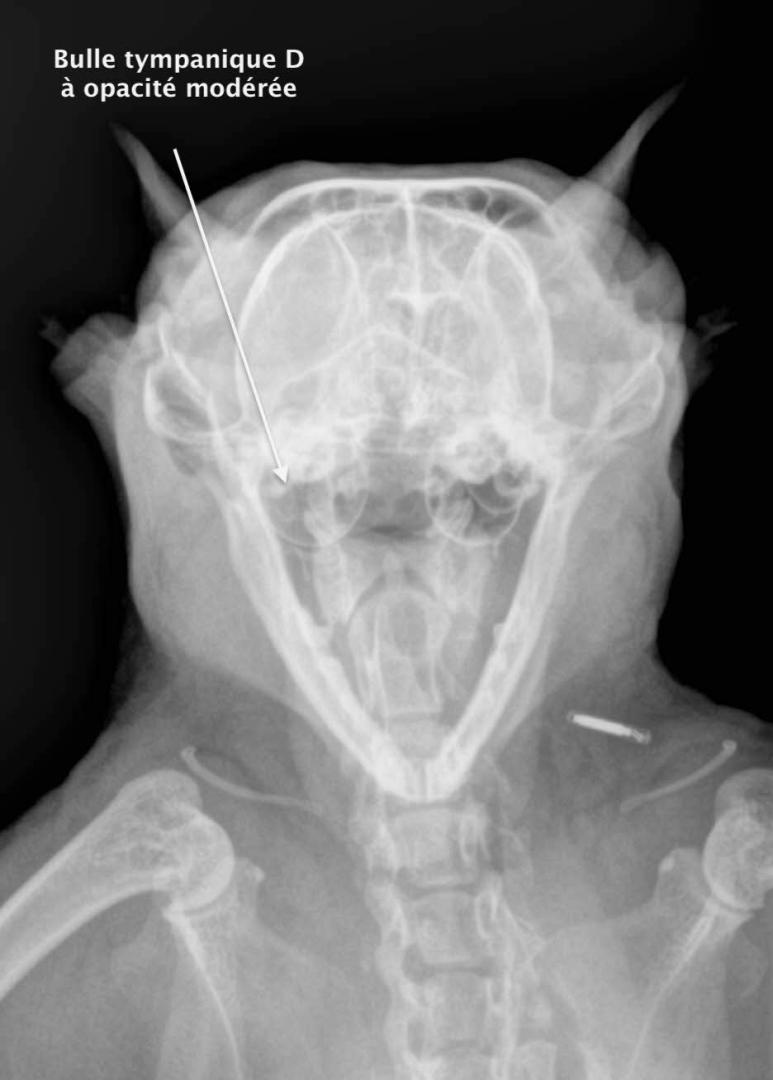

La trépanation de la bulle tympanique:

Cette technique chirurgicale consiste à perforer la paroi de la bulle tympanique et nettoyer son contenu. La chirurgie est nécessaire lors d'otite moyenne (accumulation de liquide dans la bulle tympanique) qui ne régresse pas avec un traitement médical.

Le diagnostic peut se faire par radiographie (cf images joints) mais l'examen de choix reste le scanner ou l'IRM si on souhaite une exploration fine de l'oreille interne.

A noter que les images présentes ici sont celles d'un chaton qui présente une otite moyenne droite modérée qui a été soignée à l'aide d'un traitement anti-inflammatoire et antibiotique.

Radio rostrale pour l'exploration des deux bulles tympaniques